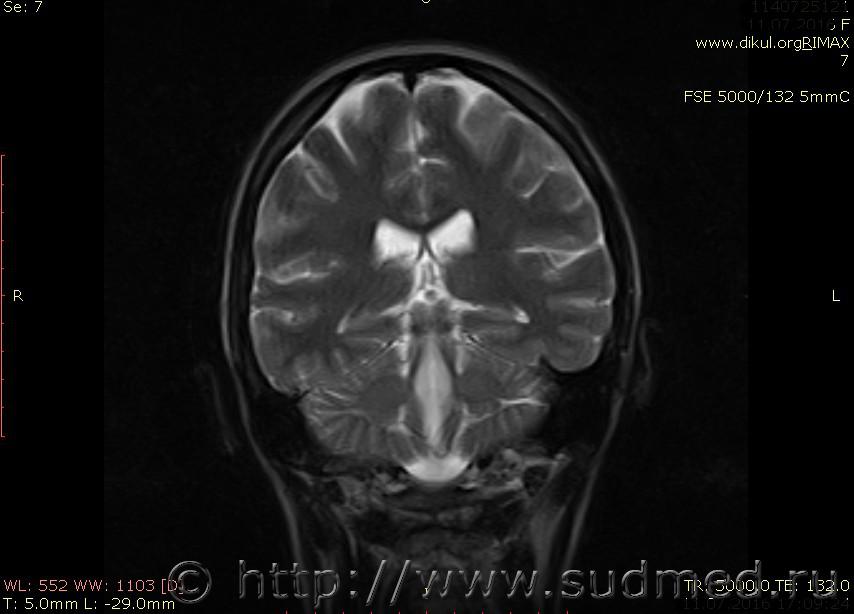

МРТ головного мозга показало: МР-данных за наличие очаговых изменений в веществе головного мозга на момент исследования не выявлено. МР-признаки нарушения соотношения в атланто-осевом суставе. Определяется ассиметрия положения зубовидного отростка С2 относительно боковых масс С1(справа 6,5; слева 4 мм.)

Сама по себе эта информация даёт основания подозревать вывих первого шейного позвонка, но однозначно не свидетельствует о наличии вывиха. Нужно смотреть на снимках наличие реакции со стороны мягких тканей, в т.ч. связочного аппарата, нужно анализировать особенности неврологической патологии, её динамику и проч.

Запрошен электронный вариант снимков из учреждения, где делалось МРТ. Т.к. с самого снимка делать копии не получается,очень мелкие кадры. Завтра попробую вставить в сообщение. (Но СМЭ снимок не смотрел, смотрел только мед.карту, в которой находилось описание МРТ).

Посмотрите пожалуйста снимки, надеюсь на них видны позвонки С1,С2?

Прошу прощения, попробую снова прикрепить файлы. Данные учреждения и пациента убраны.